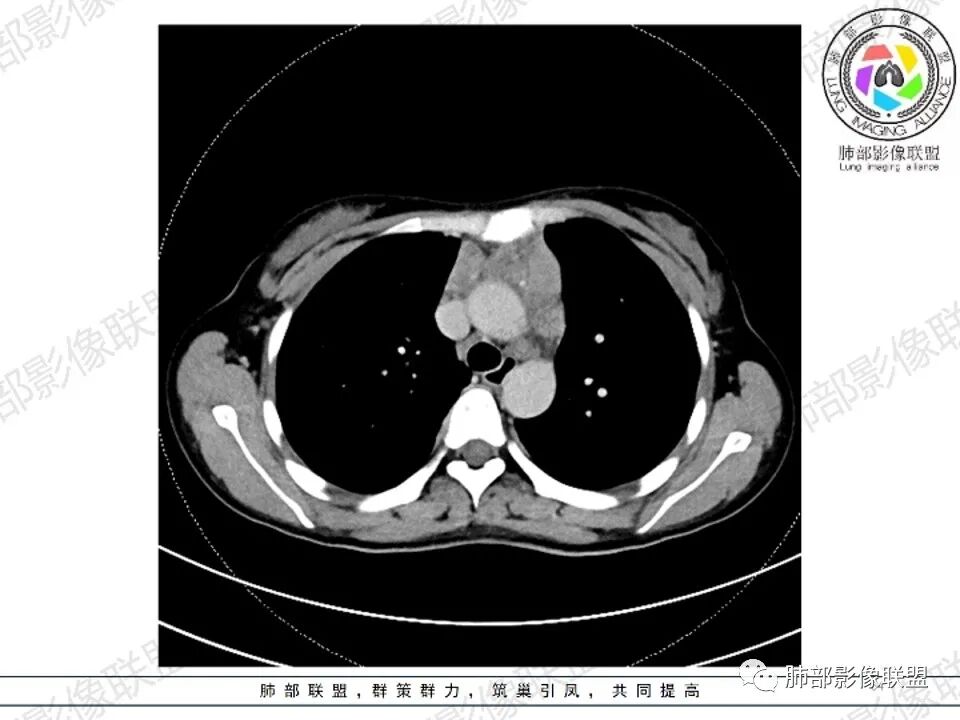

女,27,间断头晕、乏力3年,左眼视物模糊2月。贫血。胸部CT:前纵隔不规则肿块,多结节融合,边界不清,沿主动脉及肺动脉间隙生长,平扫密度欠均匀,增强扫描可见多发低密度坏死,纵隔血管供血穿行,腋窝多发大小不等淋巴结肿大。考虑恶性病变,胸腺癌?肉瘤?淋巴瘤?鉴别胸腺瘤、结节病等。

临床:年轻女性,慢性病程,多系统病变,头晕,贫血,视物模糊。

CT:定位纵膈病变,前中纵隔多发肿块,质软,塑形,密度不均匀,边界清楚。增强不均匀强化,坏死边界清楚,血管漂浮征。双侧腋下多组淋巴结肿大,明显异常强化。

考虑淋巴瘤可能。

2.影像显示前纵隔不规则块状影,依势贴附心脏大血管旁,密度不均,边界不甚清楚,有结节融合感。

3.病灶轻度不均匀强化,可见血管穿行,散在液性低密度区。

双肺门未见肿大淋巴结。

4.双侧腋窝区见增大淋巴结,边界清楚。

1.年轻女性,前纵隔不规则块状影,密度不均,边界不甚清楚,有结节融合感,轻度不均匀强化,可见血管穿行,最常见最符合的无疑是淋巴瘤!